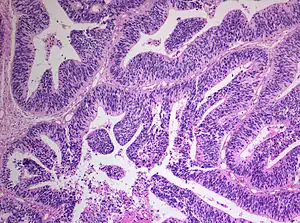

Histopathology of medulloepithelioma showing characteristic neural tube like strands.

Histologically, medulloepithelioma resemble a primitive neural tube and with neuronal, glial and mesenchymal elements.[8][9] Flexner-Wintersteiner rosettes may also be observed.[10]

Immunohistochemically, neural tube-like structures are vimentin positive in the majority of medulloepitheliomas.[11] Poorly differentiated medulloepitheliomas are vimentin negative.